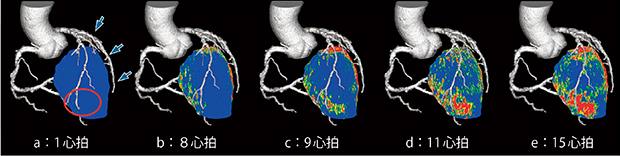

本症例の治療前の外膜側を心拍ごとに見ると,8心拍ではRCA,LCXからの血流で中隔,側壁が染まっているのに対し,心尖部前壁は高位側壁枝から側副血行路を介してLADに血流があるため血流遅延が生じ,9心拍から染まり始め,11,15心拍と逆行性に染まる様子がわかる(図6)。

図6 4Dフュージョン画像(治療前外膜側)

RADやLCXから造影されている下壁や側壁は8心拍ですでに造影剤による造影効果が見られるが,高位側壁枝(↓)からの側副血行路で造影されるLAD領域(○)は9心拍あたりから染まり始め,ほかの心筋に比べ血流が遅延している。